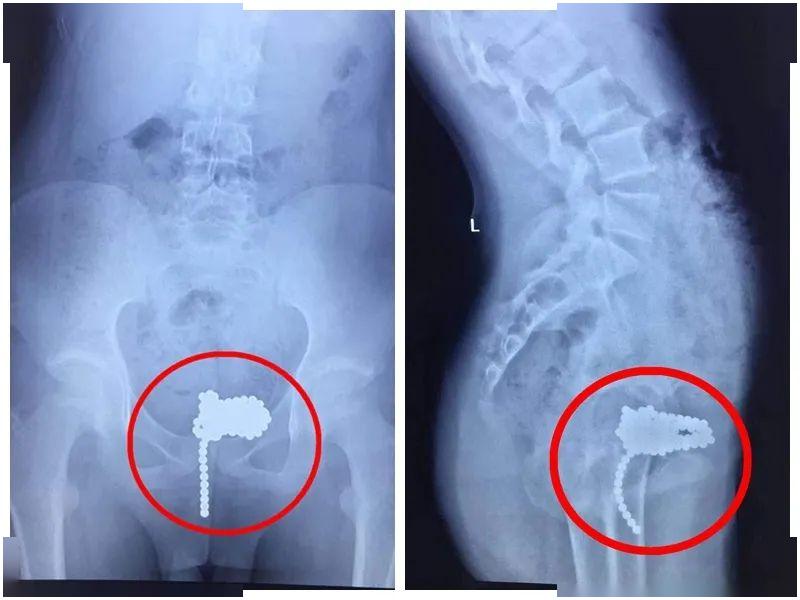

医生从小羽的腹部正侧位X线片上发现 , 上百颗珠子磁力相连 , 沿着尿道 , 一字排列 , 一路挤进膀胱后 , 又吸成一团 , 根本没有自行排出的可能 。

文章图片

整整 155颗!在小羽的尿道和膀胱里呆了3天之久 , 最后才通过医生的努力在小羽的 腹部正中开个微创小口 , 从膀胱里一次性取出所有磁力珠 。